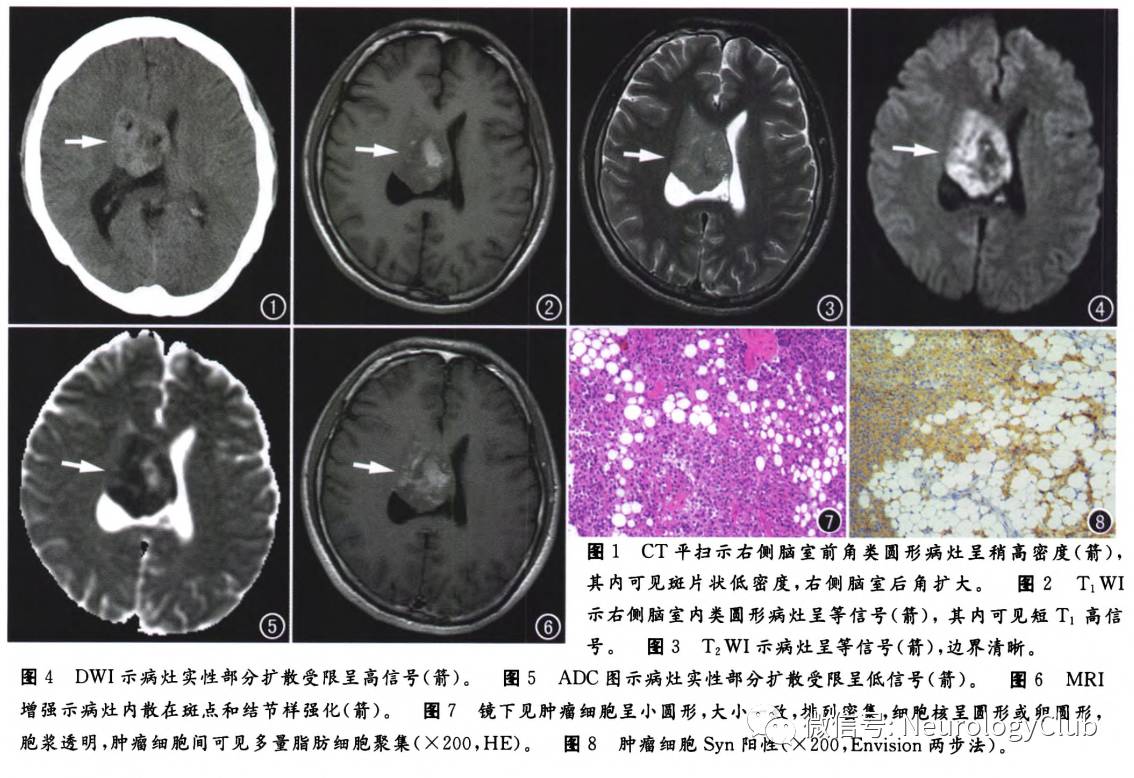

CT检查:右侧脑室前角可见4.6cm×3.8cm×2.4cm大小类圆形实性病灶,边界清楚,密度不均匀,大部分呈稍高密度,其内可见散在斑片状低密度,右侧脑室后角扩大(图1)。MRI检查:右侧脑室内可见类圆形病灶,与灰质呈等T1、等T2信号,大小约4.8cm×4.0cm×2.5cm,边界清楚,信号不均匀,其内可见团块和斑点样短T1、等T2信号,其信号强度近似头皮下脂肪(图2、3);DWI上病灶大部分呈高信号,内可见低信号(图4);ADC上大部分呈稍低信号,内可见高信号(图5);增强扫描病灶内可见散在结节、斑点及索条样中度强化,短T1信号区未见强化(图6),双侧脑室前角及右侧脑室后角室管膜轻度强化,左侧脑室受压变形,右侧脑室后角扩大。影像初步诊断:右侧脑室内占位性病变,考虑为中枢神经细胞瘤或室管膜瘤可能性大。

在全麻下行右侧脑室内肿瘤切除术,术中见肿瘤大小约5.0cm×4.0cm×2.0cm,边界欠清楚,肿瘤主体位于右侧脑室前部,基底位于透明隔前方,呈灰黄色,质软,血供丰富,有囊变,囊液呈黄绿色,内部充满细小颗粒样钙化,与丘脑、丘纹静脉粘连紧密。病理检查:大体标本切面呈灰黄色,可见颗粒样钙化和脂肪样组织;镜下示肿瘤细胞呈小圆形,大小一致,排列较为密集,细胞核呈圆形或卵圆形,胞浆透明,肿瘤细胞间可见大量脂肪细胞聚集(图7)。免疫组织化学检查:GFAP(+),S-100(+),Syn(+)(图8),NSE(+),Oli92(-),MAP-2(+),CD34(+),NF(-),Ki-67约5%。病理诊断:(右侧脑室)脂肪神经细胞瘤。